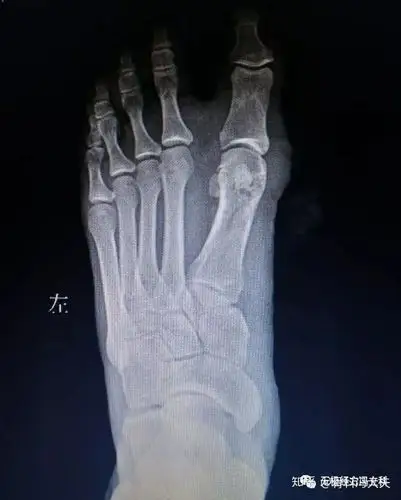

大脚骨拇外翻矫形手术